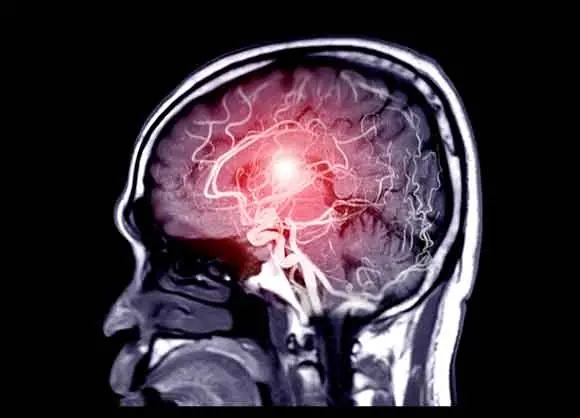

Um aneurisma cerebral é uma condição silenciosa, mas potencialmente mortal, que pode ocorrer sem aviso prévio. Ocorre quando um vaso sanguíneo no cérebro desenvolve um ponto fraco e incha, criando pressão ou, em casos graves, rompendo e causando hemorragia interna. O perigo reside no fato de que a maioria dos aneurismas não apresenta sintomas claros até que seja tarde demais. No entanto, os especialistas médicos enfatizam que existem sinais de alerta precoce que você nunca deve ignorar. Reconhecê-los pode salvar sua vida ou a vida de alguém que você ama. Aqui estão 12 sinais que podem sinalizar um aneurisma cerebral.

A detecção precoce de aneurismas cerebrais não rotos é crucial. Muitas vezes, eles podem ser tratados com cirurgia ou monitoramento cuidadoso, reduzindo o risco de uma ruptura catastrófica. Após a ruptura, as chances de morte ou danos neurológicos permanentes aumentam dramaticamente. Por isso, quando surgem sintomas, a busca rápida por atendimento médico é fundamental. O tempo é cérebro.

Técnicas como tomografia computadorizada, ressonância magnética e angiografia ajudam a diagnosticar aneurismas cerebrais antes que eles se rompam. Mas o primeiro passo é reconhecer os sintomas e agir rapidamente. Se você ou alguém que você conhece estiver apresentando alguma combinação desses sintomas, não hesite em procurar ajuda. A ação rápida pode significar a diferença entre a vida e a morte.